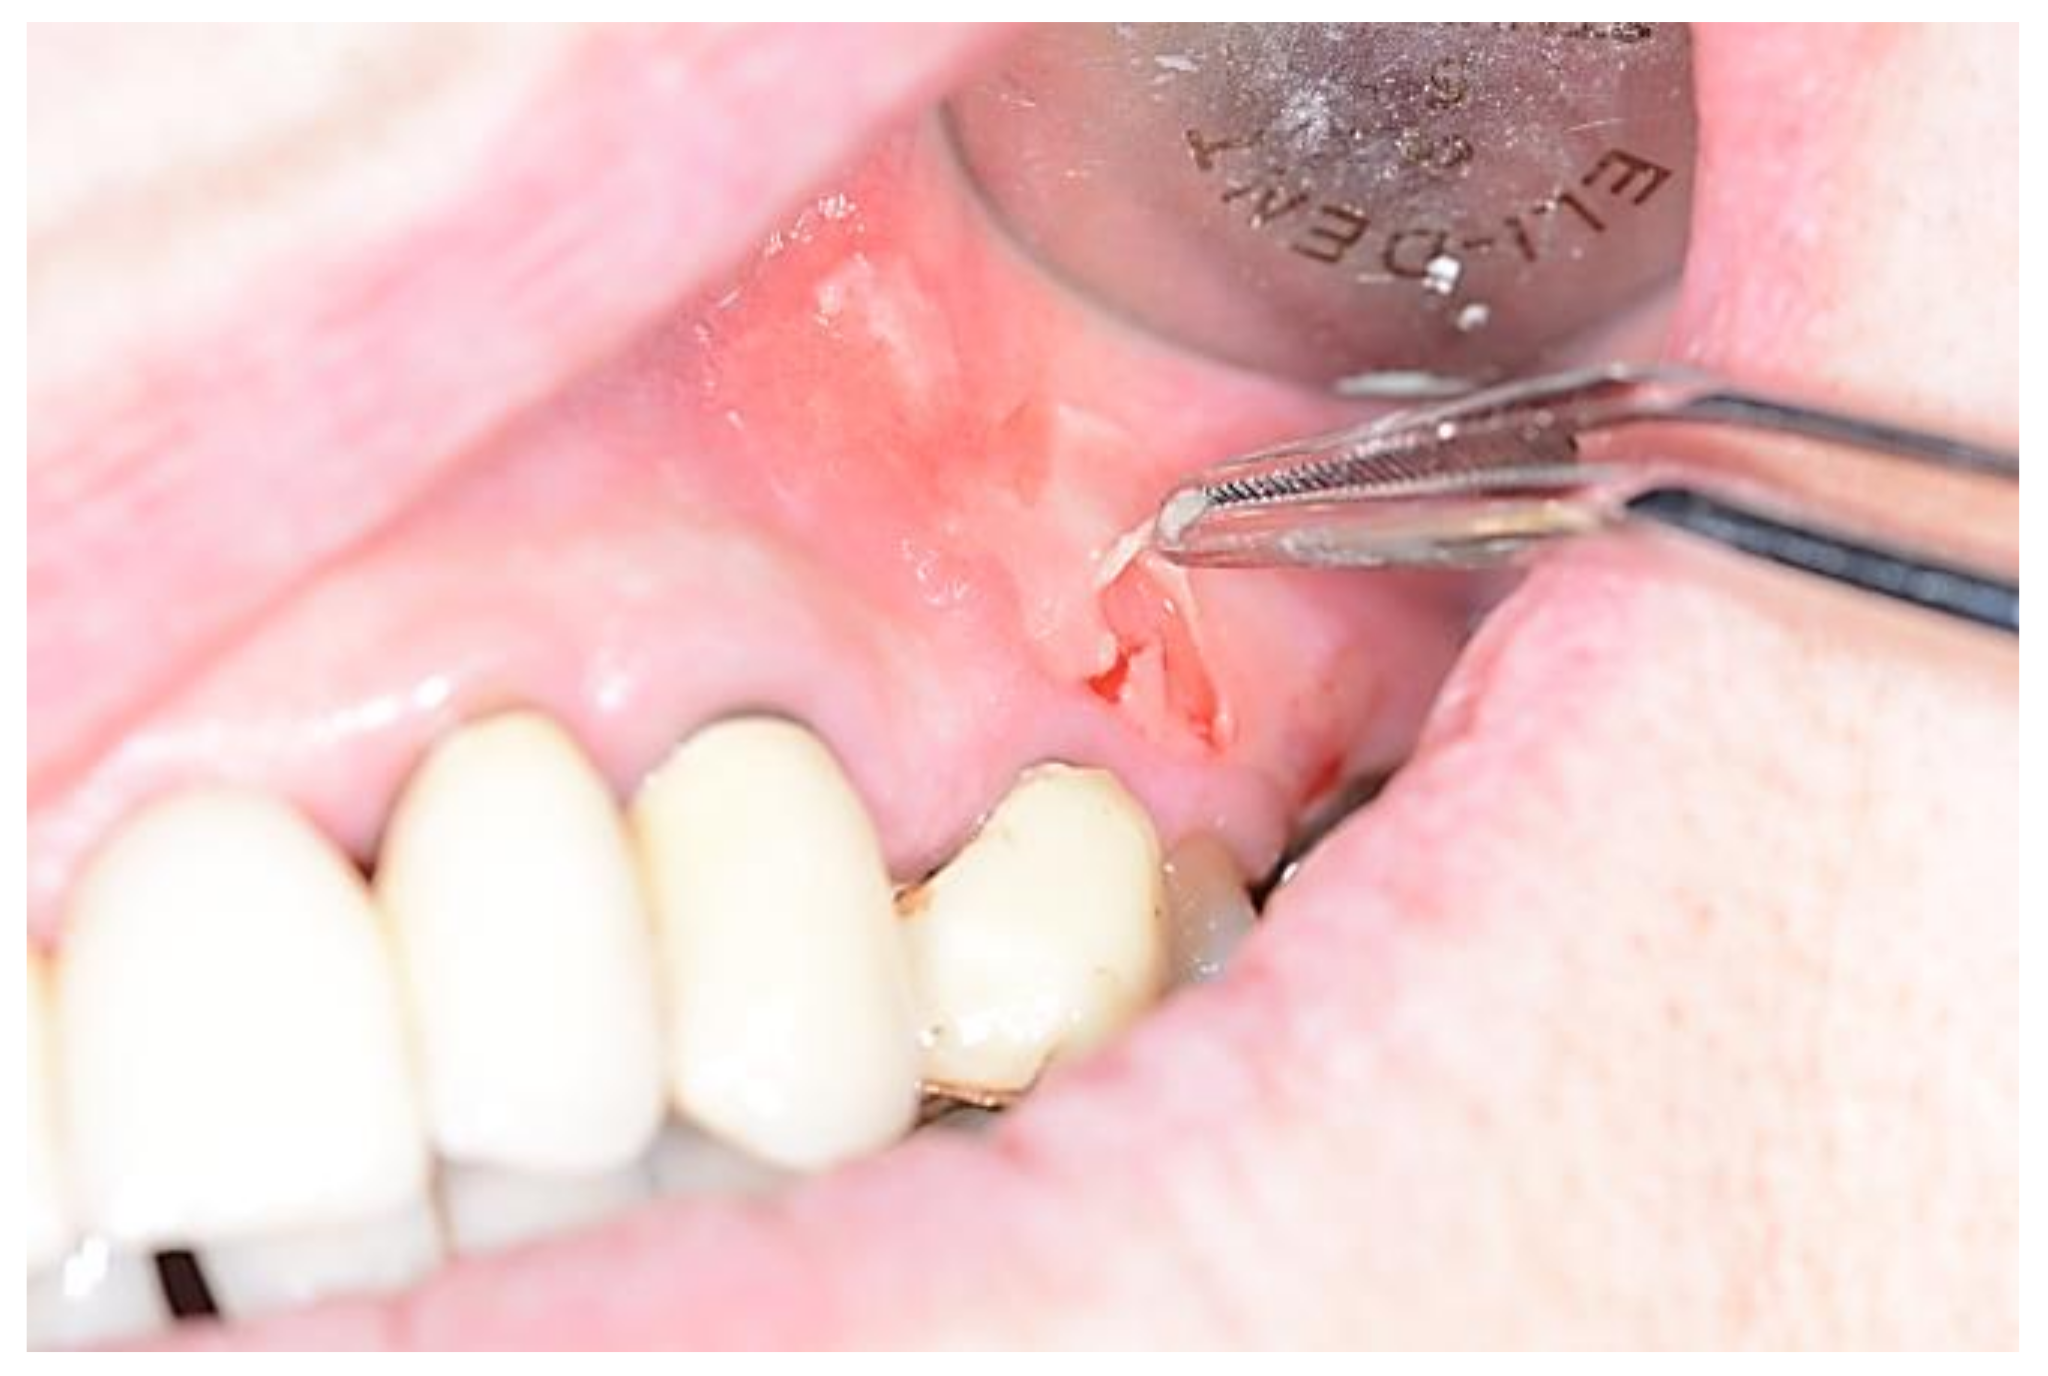

- Capodiferro, S.; Scully, C.; Ficarra, G.; De Frenza, G.; Grassi, R.; Maiorano, E.; Favia, G.; Tetè, S. Orofacial Granulomatosis: Report of Two Cases with Gingival Onset. Eur. J. Inflamm. 2007, 51–56. [Google Scholar] [CrossRef]

- Capodiferro, S.; Maiorano, E.; Limongelli, L.; Tempesta, A.; Favia, G. Cheilitis and gingivitis as first signs of Crohn’s disease in a pediatric patient. Clin. Case Rep. 2019, 7, 387–388. [Google Scholar] [CrossRef]